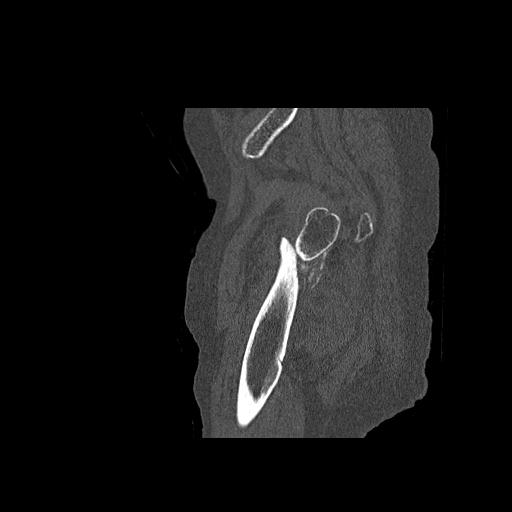

49554 3/13 膝 4R 3/16 4R 1/18 2R 78歳男性 膝蓋骨骨折